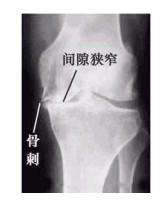

X线平片不仅为骨质增生的常规检查方法,有的学者还认为骨质增生的X线检查是追踪病情变化的金标准。

骨刺的X线片可分为五级:

0级:无改变;

1级:轻微骨赘;

2级:明显骨赘,关节间隙正常;

3级:骨赘外关节间隙中度狭窄;

4级:骨赘外关节间隙严重狭窄,伴软骨下骨硬化。